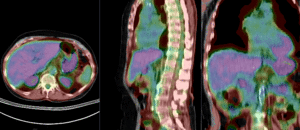

this is the fixed PET/CT image. All images are aligned into this space lleft this is the moving image. The transform is calculated by matching this to the reference image

fixed image/target moving image

• reference/fixed : baseline CT: 0.98 x 0.98 x 5 mm , 512 x 512 x 149; PET: 4.1 x 4.1 x 5 mm , 168 x 168 x 149

• moving: CT: 0.98 x 0.98 x 5 mm , 512 x 512 x 149; PET: 4.1 x 4.1 x 5 mm , 168 x 168 x 149